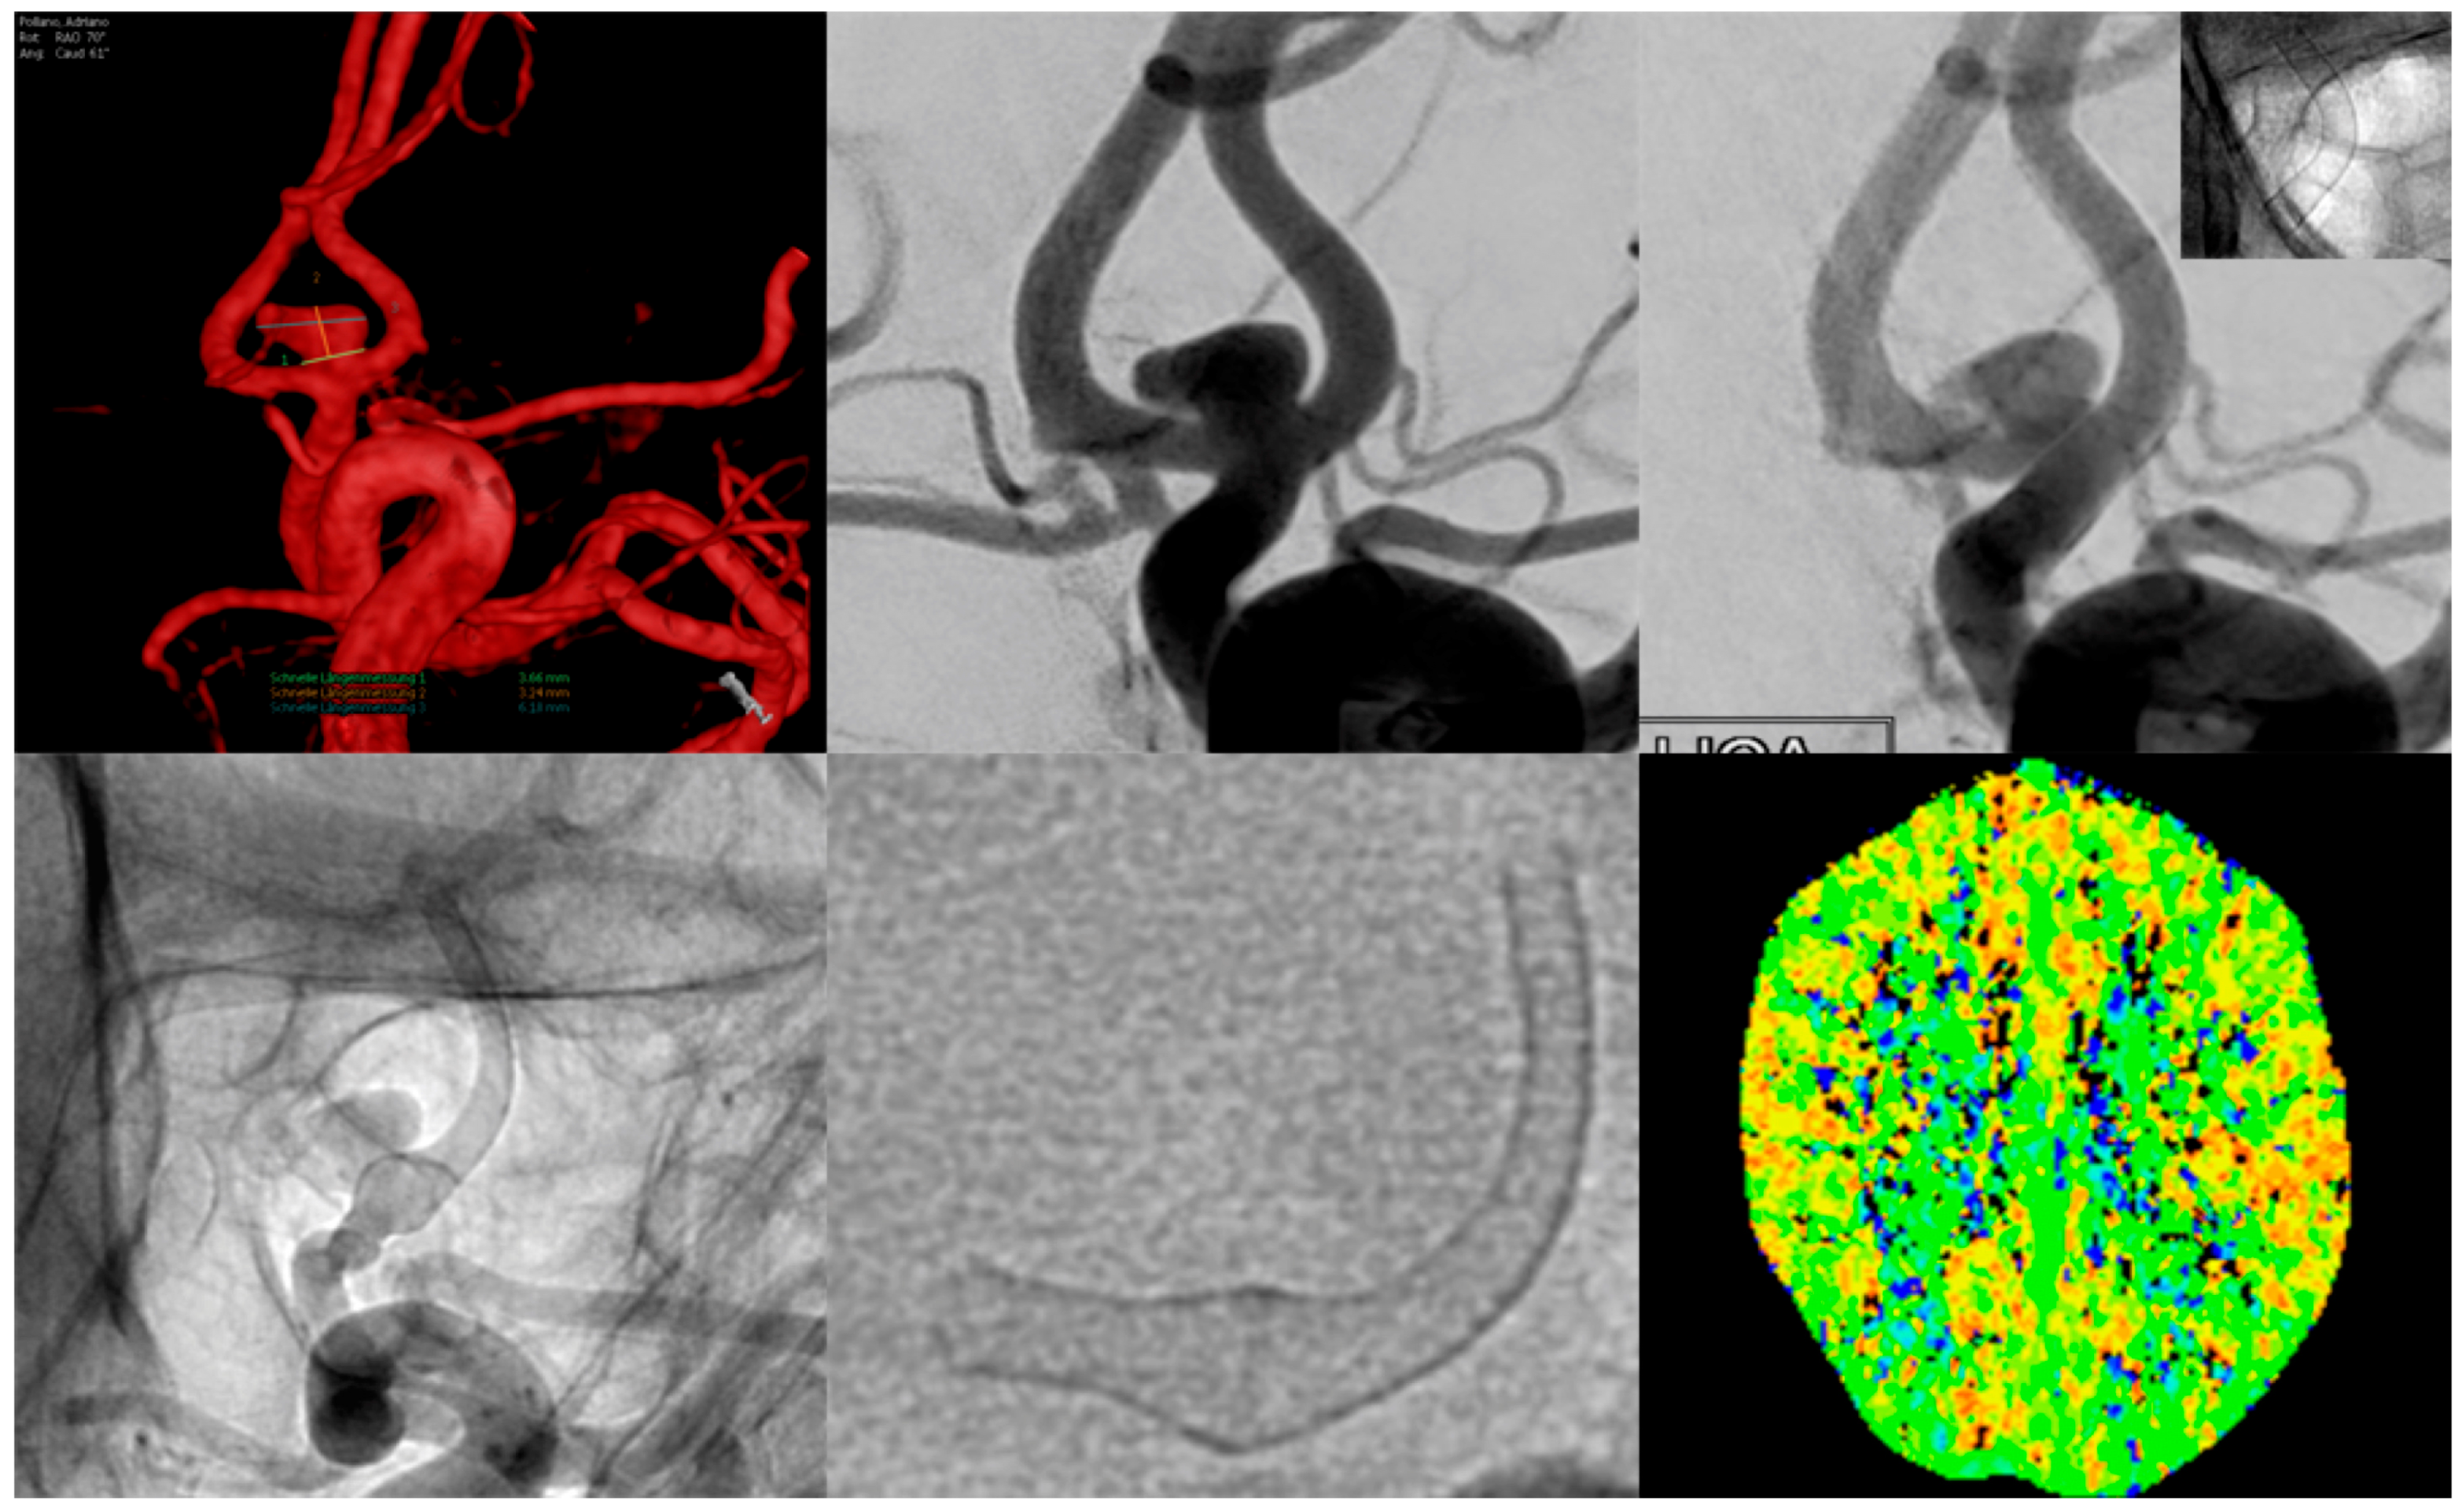

| 27 | Female | 27 | Left M1, ruptured saccular aneurysm, P&P | 3.5 | 2.8 | SVB 3.25 × 20 | 0.45 mm, 16% | >85% of the proximal (ICA) and >60% of the distal landing zone (M1) | 3 weeks | 10% | >95% |